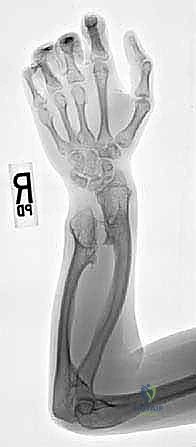

- الأشعة السينية (X-rays): لتقييم حجم الأورام، زاوية انحناء الكعبرة، ومقدار قصر الزند (Ulnar Variance).

- التصوير المقطعي المحوسب (CT Scan): لبناء نموذج ثلاثي الأبعاد للعظام يساعد في التخطيط الجراحي لعمليات القطع العظمي (Osteotomy).